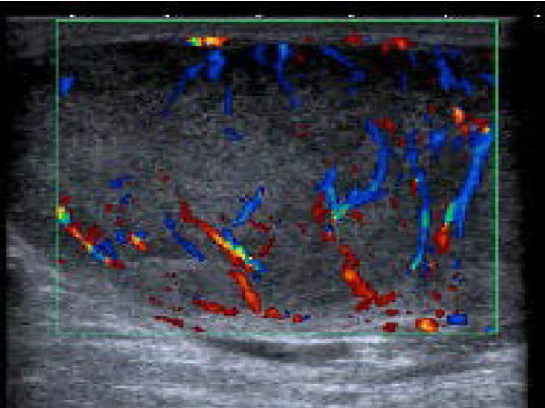

Presentamos el caso clínico de un hombre de 33 años de edad que consulta por aumento progresivo de tamaño del testículo derecho de tres meses de evolución. No refiere dolor ni sintomatología urinaria. No presenta alergias ni patologías de interés. Refiere un desarrollo psicomotriz normal sin antecedentes de criptorquidia ni hidrocele durante la infancia. Niega consumo de alcohol, tabaco u otras drogas. A la exploración física, se aprecia un aumento difuso del tamaño y consistencia del testículo derecho con transluminiscencia negativa. El testículo izquierdo es normal. No se palpan adenopatías inguinales ni en el resto de su anatomía. No presenta ginecomastia, visceromegalias ni irritación peritoneal. Decidimos realizar una ecografía testicular en Atención Primaria, apreciando una alteración de la ecoestructura de forma difusa sin presencia de quistes ni calcificaciones (figura 1). Solicitamos analítica completa con marcadores tumorales, radiografía de tórax y remitimos con carácter preferente a la consulta de Urología. Tanto el hemograma como la bioquímica básica fueron rigurosamente normales, así como la AFP, BetaHCG y LDH. La radiografía de tórax fue igualmente normal. Dado el dilatado tiempo de espera para la consulta de Urología, decidimos remitir al paciente a la Urgencia Hospitalaria con el estudio completo realizado en Atención Primaria. Se realizó una ecografía testicular reglada que confirma: “Testículo derecho aumentado de tamaño con alteración difusa de la ecogenicidad, sin calcificaciones, presenta aumento difuso de la vascularización. Proceso inflamatorio de tipo orquitis derecha, no obstante, dado el tiempo de evolución no se descarta proceso neoplásico” (figura 2). Ingresa en Urología y se realiza orquiectomía radical inguinal derecha. Anatomía patológica informa: “Seminoma clásico de diámetro mayor de 8 cm, sin evidencia de infiltración de la túnica albugínea. Restos de parénquima testicular con focos de tumor germinal intratubular. Epidídimo y borde de resección del cordón espermático sin evidencia de malignidad”. Ante dichos hallazgos, se realiza Tomografía Computerizada (TC) abdominopélvico para su estadificación: “No se observan adenopatías mediastínicas, hiliares ni axilares de tamaño significativo. Adenopatía paracardiaca derecha de 6 mm y micronódulo de 4 mm en LM. No se observan adenopatías retroperitoneales ni pelvianas de aspecto patológico. Se observan hallazgos compatibles con paniculitis mesentérica y adenopatías inguinales bilaterales de aspecto reactivo secundarias a la cirugía. Resto de estudio sin hallazgos”. Fue remitido a Oncología con el diagnóstico de seminoma puro estadio I. Dado que más del 80 % de los casos nunca recaen, en correlación con la Guía de la Asociación Europea de Urología, se decide realizar vigilancia sin necesidad de tratamiento adyuvante. Sin embargo, el riesgo pequeño, pero clínicamente significativo de recidiva, respalda la necesidad de vigilancia a largo plazo2 e iniciar radioterapia o quimioterapia basada en cisplatino, de rescate. Como las recidivas ocurren principalmente en los primeros 2 años, se recomienda el seguimiento mediante TC cada 3 meses el primer año, cada 4 meses el segundo y cada 6 y 12 meses en los años siguientes3. Nuestro paciente lleva más de 3 años de seguimiento, sin datos de recaída. Los hallazgos inespecíficos presentes en el primer TC han desaparecido y los marcadores tumorales se mantienen negativos hasta la actualidad.

La ecografía sirve para confirmar la presencia de una masa testicular y para explorar el testículo contralateral. Su sensibilidad en la detección de un tumor testicular es prácticamente del 100 % y desempeña un papel importante a la hora de determinar si la masa es intra o extratesticular. Se suelen presentar como una o varias masas hipoecoicas (seminoma) o hiperecoicas con microcalcificaciones4. Es una prueba económica y debe realizarse incluso si hay un tumor clínicamente evidente; así como en varones jóvenes que presentan masas viscerales o retroperitoneales, elevación de los marcadores tumorales séricos o en hombres con problemas de fertilidad; presenten o no, masa escrotal palpable.